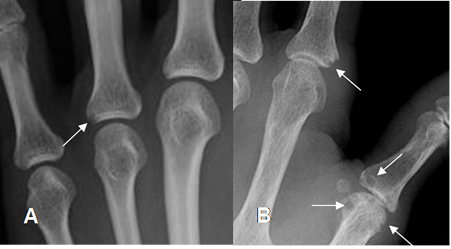

Las erosiones se aprecian como áreas radiolúcidas, relacionadas con los sitios de inserción de los ligamentos interóseos y la sinovial. Los lugares con cambios más tempranos son la base del 3º y 4 º metacarpianos, entre los huesos grande y ganchoso y el lado ulnar del ganchoso. (6). (Fig 21 y 22).

Fig 21. Artropatía reumática.

A: Rx AP de mano. Hallazgo precoz de la enfermedad, con erosión marginal.

B: Estado mas avanzado con varias erosiones en los metacarpianos y las falanges.